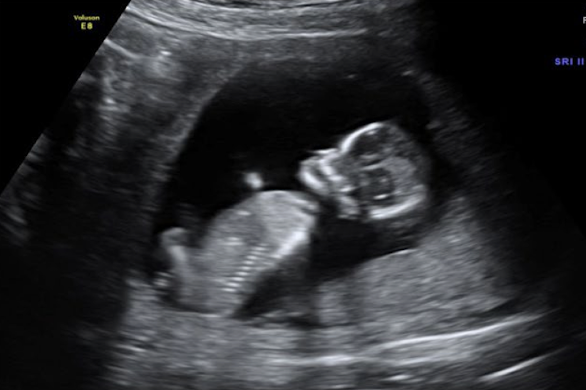

SONO: amniotic fluid

generally echo-free

can sometimes see tiny echogenic particles

blood, normal variant, vernix caseosa, meconium

presence of a dense collection, or sludge, could indicate infection